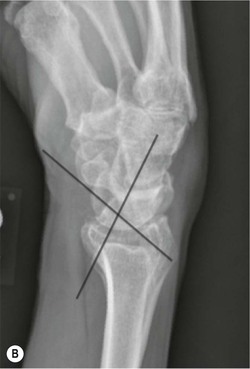

Lunate and perilunate dislocations are important injuries. In lunate dislocation, the lunate dislocates in a volar direction with loss of the articulation of the radius and other carpal bones. In perilunate dislocation, the lunate retains the articulation with the radius and the remainder of the carpus dislocates in a dorsal or volar direction. PA radiographs show an abnormal triangular appearance of the lunate. Differentiation of lunate versus perilunate dislocation is best made on a lateral radiograph. Both injuries may be associated with scaphoid (or other carpal) fractures, which indicates a greater degree of wrist instability.